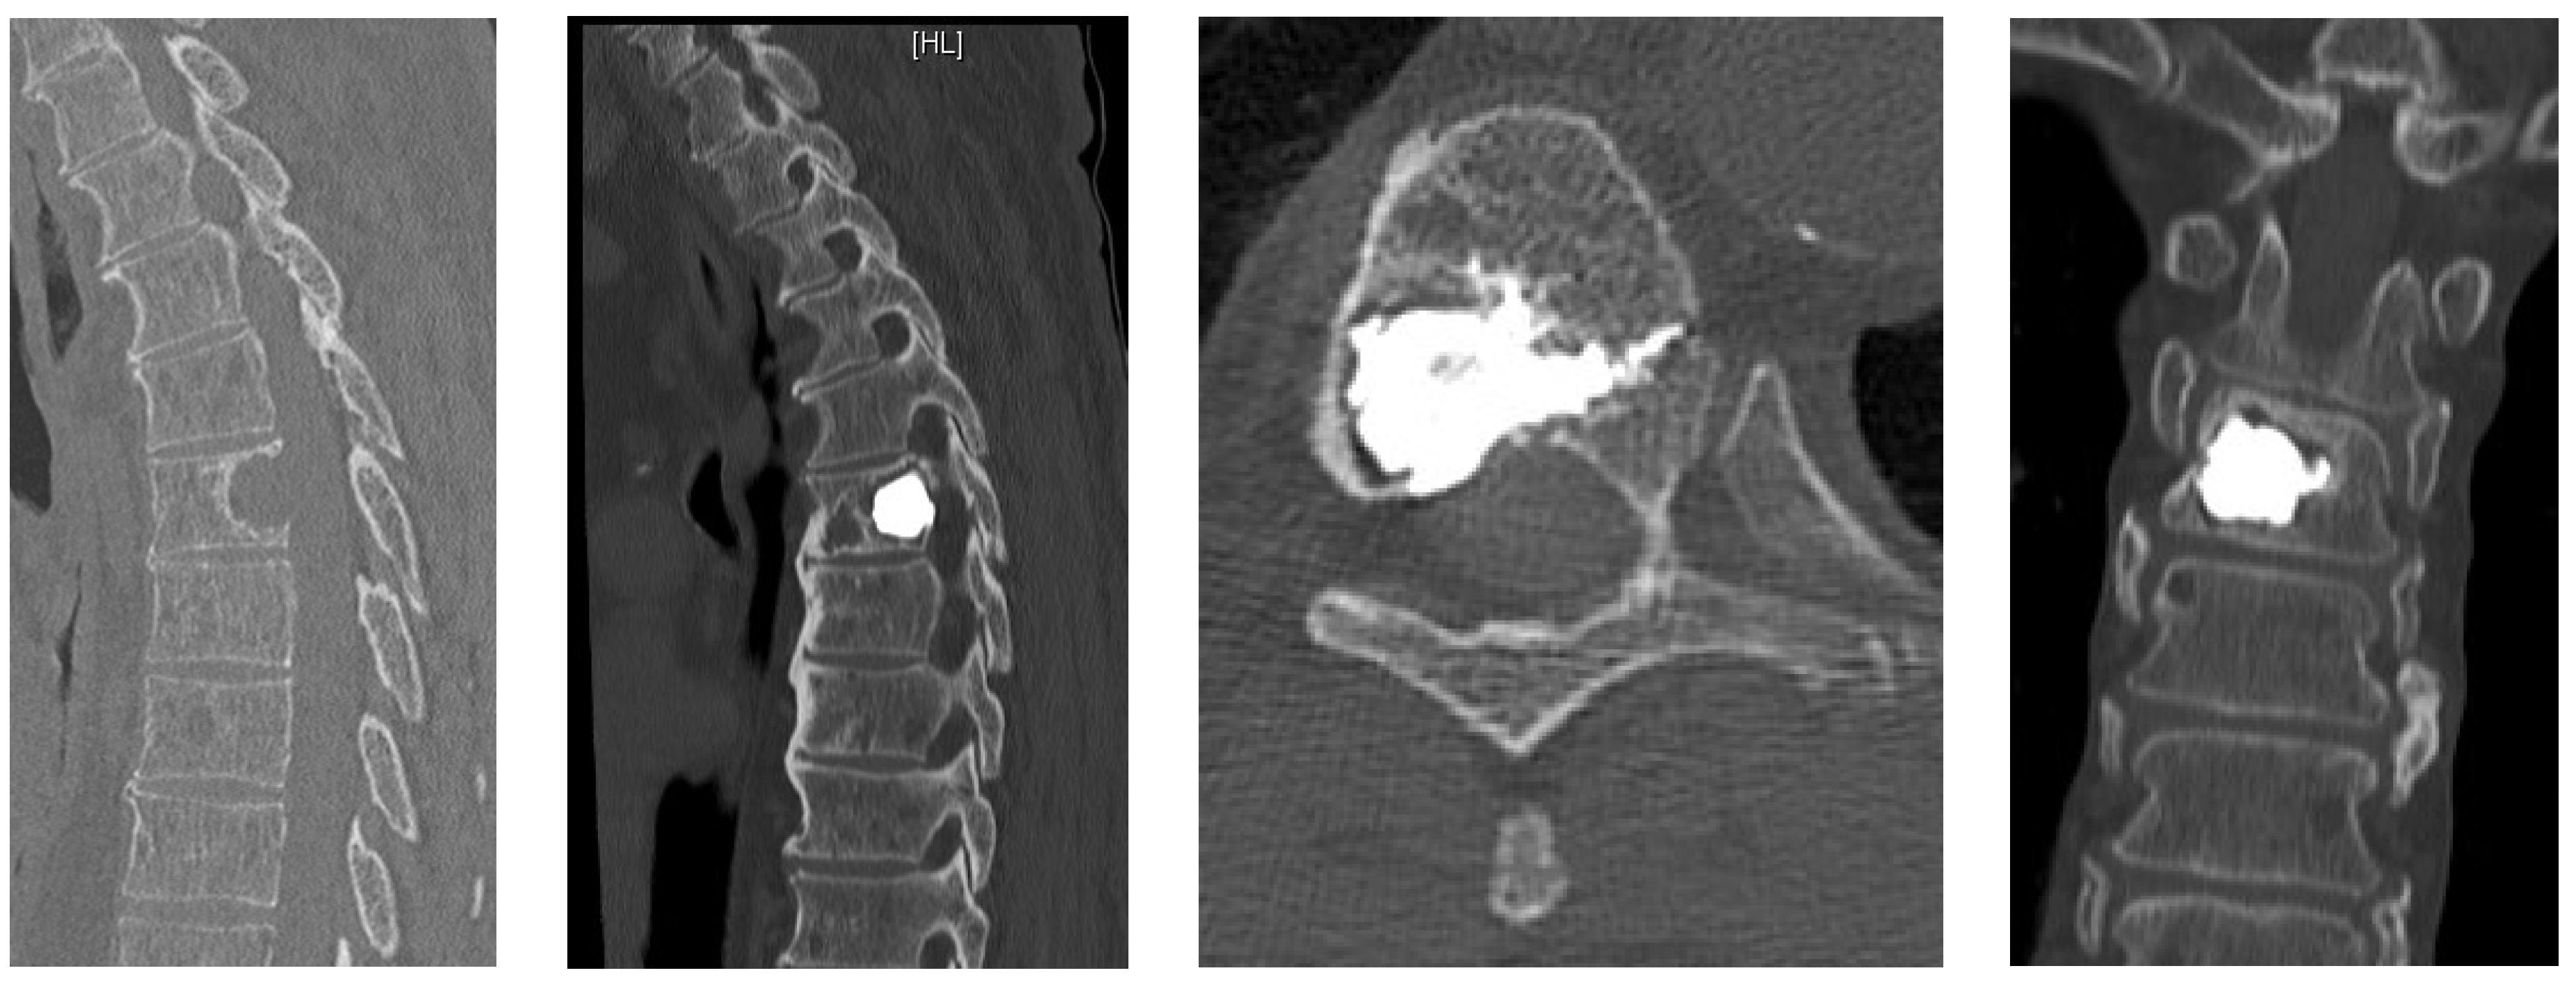

- Unrestricted reconstruction of datasets with views along the path of the needle with planning in 3D and 2D reconstructions (Figure 1).

- Posterior percutaneous kyphoplasty for cervical spine metastases (Figure 2); case of C2-C3 kyphoplasty.

- Metastatic lesions of C1 are extremely rare, and their treatment by percutaneous cement augmentation is considered to be a technically challenging procedure due to complex anatomy. We also performed percutaneous kyphoplasty in a painful osteolytic lesion located on the left lateral mass of C1 through a posterolateral approach using a 3D CT scan intra-operative navigation system and fluoroscopy (Figure 3) [22].